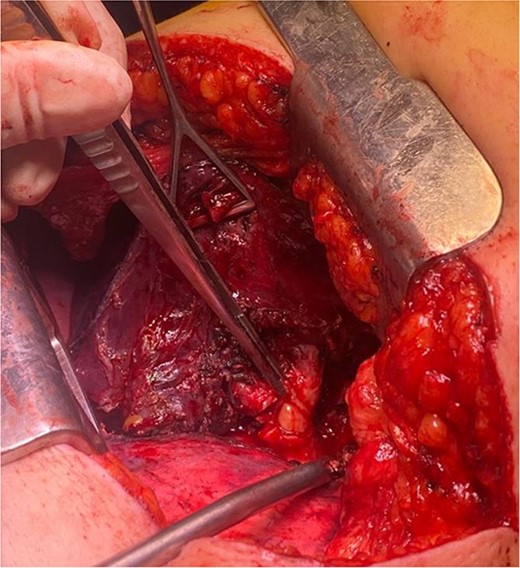

The patient underwent left-sided thoracotomy and upper lobectomy due to severe parenchymal inflammation and necrosis of the left upper lobe, with histopathology confirming a well-circumscribed adipocytic lesion consistent with lipoma measuring ~9.1 × 6.9 × 9.3 mm in the bronchus (Figs 3 and 4). Adjacent lung tissue exhibited organizing pneumonia and bronchiectasis. Post-operatively, she recovered well and was discharged home in stable condition on the fourth day.